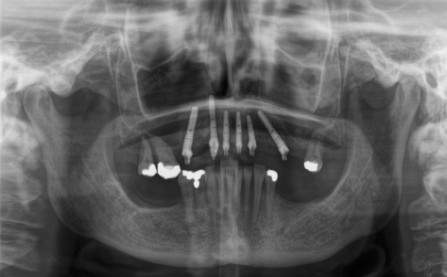

Treatment Type: Sky Fast & Fix Implants( Teeth In One Day)

A Treatment Plan for Mrs C was devised using the SKY ‘Fast and Fixed’ system. Six implants in the upper jaw were inserted (known as All-on-six) and in a similar manner four implants were also fixed to her lower jaw (All-on-four) to secure a full set of new teeth on a fixed bridge in JUST 1 DAY! The advantages of using this technique for Mrs C were several:

Prior to the day of her surgery, some low-dose X-rays of Mrs C’s jaw were taken, followed by a CT scan. The latter provided our dentist with information regarding her bone quality, position of her nerves and sinuses. On the actual day, the surgery was performed under local anaesthetic, with the implant placement and any extractions taking about 2 hours for each jaw. Later in the day a temporary bridge (full arch fixed prothesis) was attached to the dental implants. This provisional restoration of her teeth meant that no one noticed the treatment. The bridge, although temporary, looked very natural, since our dentist had taken care refining the bite and aesthetics. Before going home Mrs C booked a review appointment with us for a fortnight later. This was to check that all is well and to see if any minor modifications were needed.